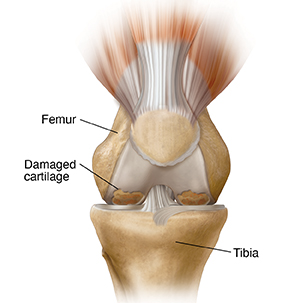

A joint is a place where two bones meet. The knee is called a hinge joint. This joint is formed where the thighbone (femur) meets the shinbone (tibia). A healthy knee joint bends freely. Knee osteoarthritis is a condition where parts of the knee joint wear out. This can lead to pain, stiffness, and limited movement.

Every joint contains a smooth tissue called cartilage. Cartilage cushions the ends of bones and helps bones in a joint glide smoothly against each other. Knee osteoarthritis occurs when cartilage in the knee joint starts to break down and wear away. Bones may become exposed and rub together. The cartilage may become irritated and rough. This prevents smooth movement of the joint and can lead to pain.